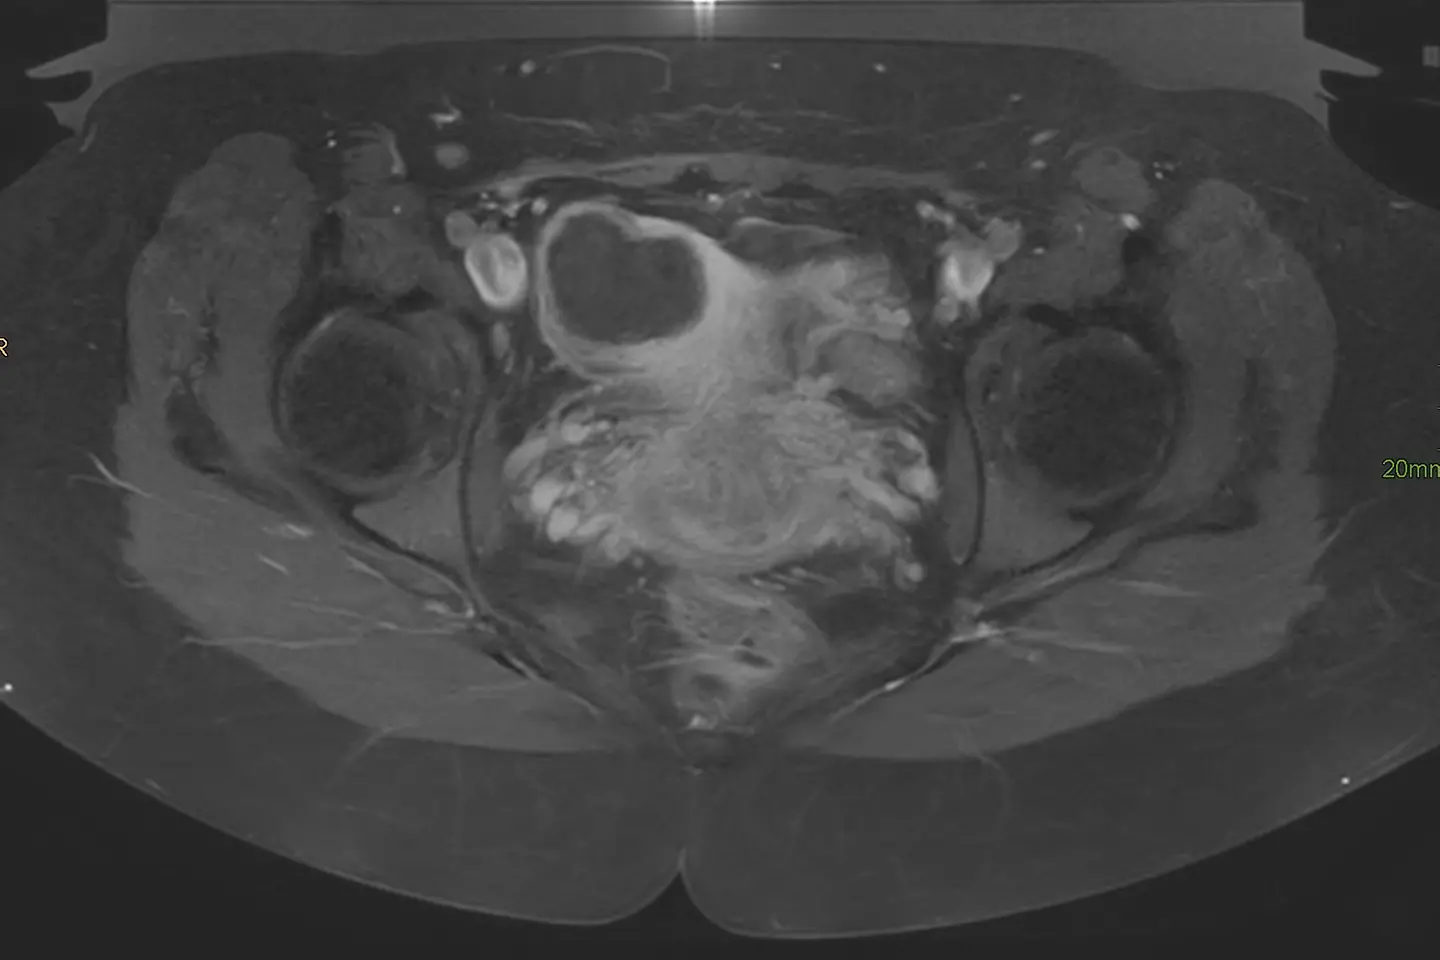

MRT-Aufnahme Myom

Die Behandlung von Gebärmuttermyomen mittels MR-HIFU ist keine Regelleistungen der Krankenkasse, das Marienhospital muss für jeden Eingriff einen Antrag stellen. Nicht so bei Versicherten der Barmer. Kommt bei ihnen eine Therapie mittels MR-HIFU infrage, dann kann diese direkt auf Veranlassung der behandelnden Ärzte erfolgen, ein Antrag ist nicht notwendig. „Durch die Kooperation mit dem Marienhospital erhalten unsere Versicherten schnellen Zugang zu schonender Spitzenmedizin, die Klinik profitiert von weniger Bürokratie und kann sich voll der medizinischen Behandlung widmen“, erklärt Barmer Landesgeschäftsführer Winfried Plötze. Ob eine Patientin mit dem MR-HIFU behandelt werden kann, prüfen Fachärzte des Marienhospitals. "Unter anderem spielen Größe und Lage des Myoms bei der Entscheidung eine Rolle", erklärt Prof. Markus Zähringer, Ärztlicher Direktor der Klinik.